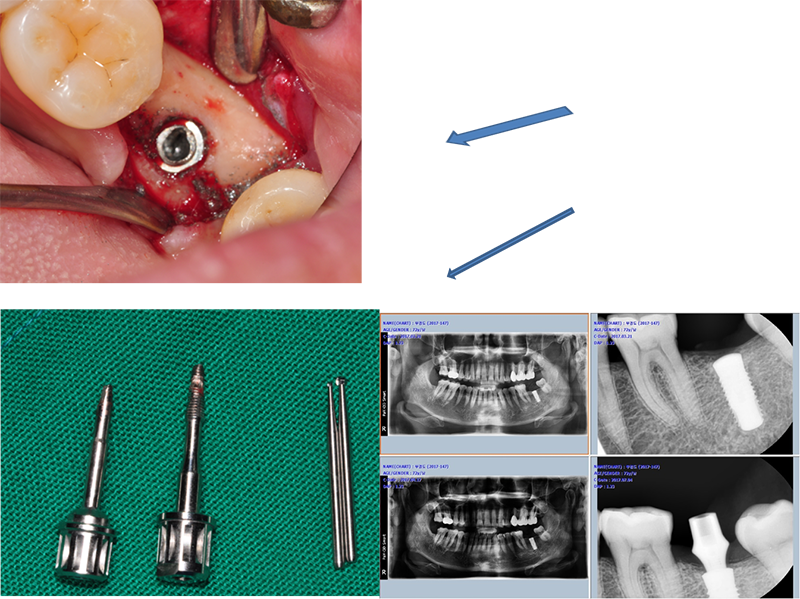

¼ö¼úÇÏ°í ¹Ù·Î convertible abutmentÀÎ Ezc ab¸¦

ÀåÂøÇϰí ÀλóÀ» 䵿Çß´Ù. Àӽú¸Ã¶¹°À» ¸¸µé±â À§Çؼ´Ù.

Ezc convertible

abutment¸¦ À§Ä¡½Ãų ¶§ ¼ö¼ú Á÷ÈÄÀ̹ǷΠÀÕ¸öº¸´Ù 1.0~1.5mm ÇϹ濡 À§Ä¡½Ã۸é ÁÁ°Ú´Ù.

ÀÌ ÀÓ»ó ÄÉÀ̽º´Â ºê¸´Áö ŸÀÔÀ»

½Ì±Û ŸÀÔÀ¸·Î ¹Ù²ãÁÖ±â À§ÇÑ ÀÛ¾÷ Áß ÀÏ¾î³ ÀÛÀº ¼Òµ¿À» ±â·ÏÇß´Ù.

¾î¹þÀ» Ç®´Ù°¡ Ç÷¿Æû¿¡ ÀÖ´Â

Çí»ç°¡ ¸Á°¡Á³´Ù. Ç® ¼ö°¡ ¾ø¾ú´Ù. 4.4 mm ³»°æÀ» °¡Áø solid ab ü°á µå¶óÀ̺긦 ÀÌ¿ëÇϱâ·Î Çß´Ù.

¸ÕÀú Ezc ¾î¹þÀÇ Á÷°æÀ» ´ÙÀ̾Ƹóµå ¹ö·Î »ì¦ ´ÙµëÀº ´ÙÀ½, ½½·ÔÀ» ¸¸µé°í, À̰÷¿¡ solid ab µå¶óÀ̹ö°¡ »ðÀԵǵµ·Ï ÇÑ´Ù. µ¹¸®¸é ½±°Ô Á¦°ÅµÈ´Ù.